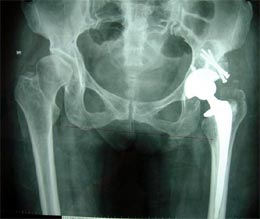

病例五

患者男性,76岁,十年前曾右髋关节置换术,术后逐渐出现髋关节疼痛活动受限,

X线片显示股骨假体和髋臼均松动,股骨近段有骨缺损。

行翻修手术。术中发现臼底已经穿透入盆腔,用钛网和植骨方法修复髋臼,股骨侧用非骨水泥假体固定。